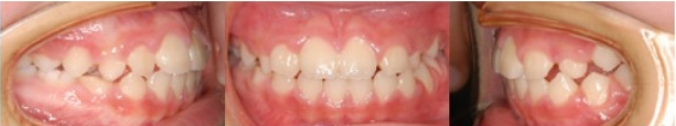

본원의 어린이 부정교합 교정 턱끝변화

어린 자녀에게서 부정교합 양상이 보인다면

교정전문치과에 내원하여

치료시기를 미리 진단받으시는게 좋습니다.

연세굿데이는 아이들의 치료시기를 진단할 때

X-Ray와 성장판 검사를 통해 분석합니다.

이는 향후 예측되는 성장량을 파악하고,

치료의 적기를 판단하는데 도움이 됩니다.

성장시기를 활용한 시기야 말로 바른 치열과

균형잡힌 얼굴성장을 유도하기에 적절하며,

후에 일어날 부정교합 예방에도 효과적이니

성장기교정 늦지않게 시작하시길 바랍니다.^^